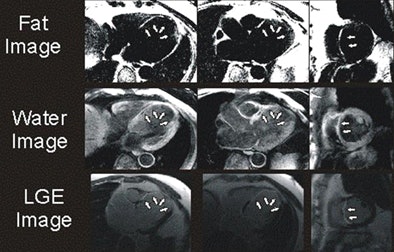

| Above, four-chamber, three-chamber, and short-axis images of a patient with fat deposition in segments of myocardial infarction. Precontrast fat-water separation imaging shows midwall fat deposition that is hyperintense in fat images and hypointense in water images. Late gadolinium-enhanced (LGE) infarct imaging shows an apical-septal chronic myocardial infarction. Below, fat-water separation imaging color overlay. Colored fat displayed on grayscale water images from two patients with chronic myocardial infarctions. Arrows point to midwall fat deposition. Images courtesy of Dr. James Goldfarb. |

The study examined 25 patients with LV MI (mean age, 64.3 years; range, 43.2-82.1 years) using a 1.5-tesla MRI scanner system. Protocols included volumetric cine, fat-sensitive, and late gadolinium-enhanced (LGE) infarct imaging. Water-fat separation was performed by using a three-point Dixon reconstruction from in- and opposed-phase black-blood gradient-echo images.

Fat deposition was seen in 68% of patients in areas of chronic MI. Patients with fat deposition on imaging had larger infarctions (30.0 mL ± 15.1 [standard deviation] versus 14.8 mL ± 6.1; p = 0.002), less wall thickening (2.3% ± 20.0 versus 37.8% ± 34.4; p = 0.003), and impaired endocardial wall motion (2.9 mm ± 2.0 versus 5.8 mm ± 2.6; p = 0.007) compared to normal patients, the group reported. In addition, the volume of fat deposition correlated with infarct volume, LV ejection fraction, LV end-diastolic volume index, and LV end-systolic volume index.

"Since fat deposition was found solely in myocardial segments with or directly adjacent to MI, one might infer that LV MI is a precursor to LV myocardial fat deposition," Goldfarb and his team wrote, adding that serial imaging over several years would be necessary to test the hypothesis. "We also found that fat deposition was predominately midmyocardial or midepicardial, whereas results of prior autopsy and CT studies suggest that fat deposition almost always affects the subendocardium."